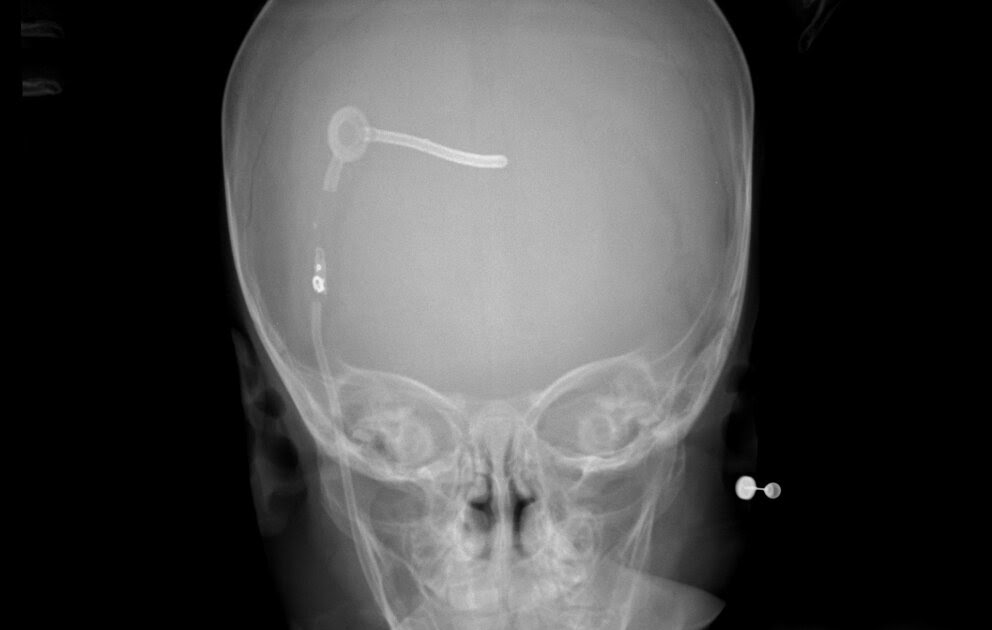

La hidrocefalia con presión normal se caracteriza por una alteración de la marcha, incontinencia urinaria, demencia, ventrículos encefálicos agrandados y una presión de líquido cefalorraquídeo normal o ligeramente elevada. (Véase también Generalidades sobre el delirio y la demencia y Demencia ).. El Kit Válvula Essential BurrHole Baja Adulto ofrece componentes de calidad a un bajo costo, presentados en un kit fácil de usar. Disponible en dos configuraciones y varias presiones, el diseño de cama plana está destinado para presiones baja y media, mientras que el Burr Hole es apto para presiones baja, media y alta.

The aim of our study is to evaluate a number of patients diagnosed with adult chronic idiopathic hydrocephalus who were treated with a CSF shunt at our centre between 2006 and 2009 through.. La hidrocefalia, conocida como “agua en el cerebro” es un trastorno causado por la acumulación de líquido cefalorraquídeo en las cavidades (ventrículos) de la profundidad del cerebro. Esto causa un aumento en el tamaño de los ventrículos y la presión sobre el cerebro que lleva a un daño cerebral. Las válvulas ventrículo-peritoneales.